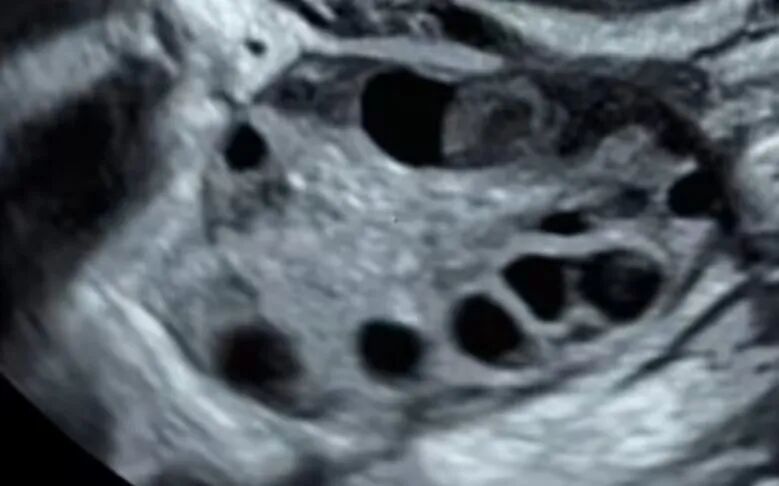

冷冻卵子:将女性成熟的卵子取出后直接冷冻保存。

冷冻胚胎:将卵子和精子结合形成受精卵(胚胎) 后冷冻保存。